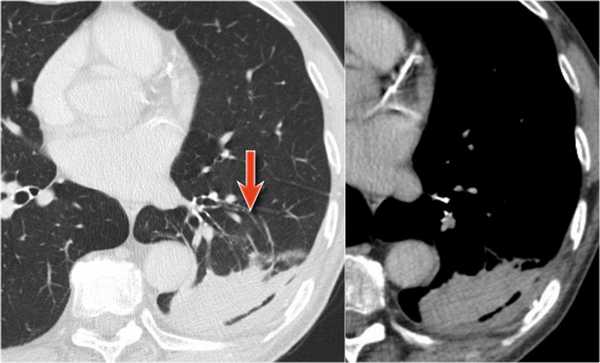

На ниже представленной рентгенограмме пациента с карциноматозом плевры левое легкое полностью компрессируется плевральной жидкостью (левый гемоторакс). В выше представленных случаях был обтурационный ателектаз, а в этом компрессионный, что лучше визуализируется на КТ (синяя стрелка). КТ данному пациенту также проводили по причине легочного эмболизма (красная стрелка).

Округлый ателектаз

- утолщение плевры

- образование, исходящее из плевры

- симптом хвоста кометы

Локальный плеврит является причиной утолщения плевры. Далее происходит инвагинация субплевральной легочной паренхимы с характерным дугообразным искривлением сосудов, и ателектаз принимает округлую форму. Симптом хвоста кометы — это симптом, который визуализируется в виде кометообразного хвоста из сосудов и воздухоносных путей, направленных к корню легкого.

На боковой рентгенограмме выявляется образование, которое исходит из плевры. На первый взгляд — это образование, исходящее из плевры.

Далее перейдите к оценки КТ-снимков.

На КТ четко выявлено, что это образование легкого. Для многих данные изменения на КТ заставили бы задуматься о раке легкого. Красной стрелкой указана утолщение плевры, а синими стрелками указаны сосуды вокруг данного образования, что называют хвостом кометы.

Всякий раз, когда встречается образование, сочлененное с плеврой, а также похожее на рак легкого, то не забудьте об округлом ателектазе.